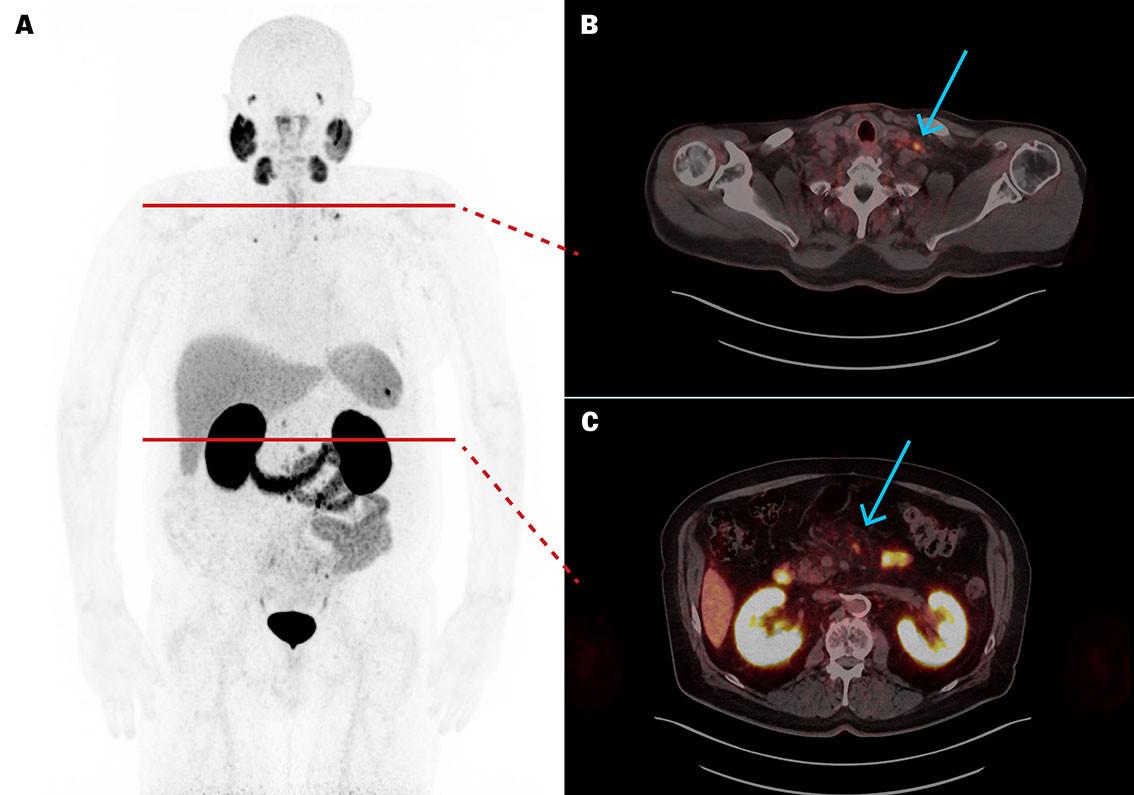

PSA i plasma (p-PSA, referanseområde 0–4,0 µg/L for menn ≥ 60 år) var 154 µg/L og PSA-doblingstiden var 4,5 måneder. PET/CT med det radiofarmasøytiske sporstoffet prostataspesifikt membranantigen radioligand (PSMA-RL) merket med Gallium-68 ([⁶⁸Ga]PSMA-11) viste meget høyt opptak i utbredte metastatiske lymfeknuter i bekken, abdomen, toraks og hals, samt en solitær skjelettmetastase i høyre krageben (figur 1). Opptaket indikerte at det kunne ligge til rette for behandling med PSMA-ligand merket med den beta-emitterende radionukliden Lutetium-177 ([¹⁷⁷Lu]PSMA-RL).